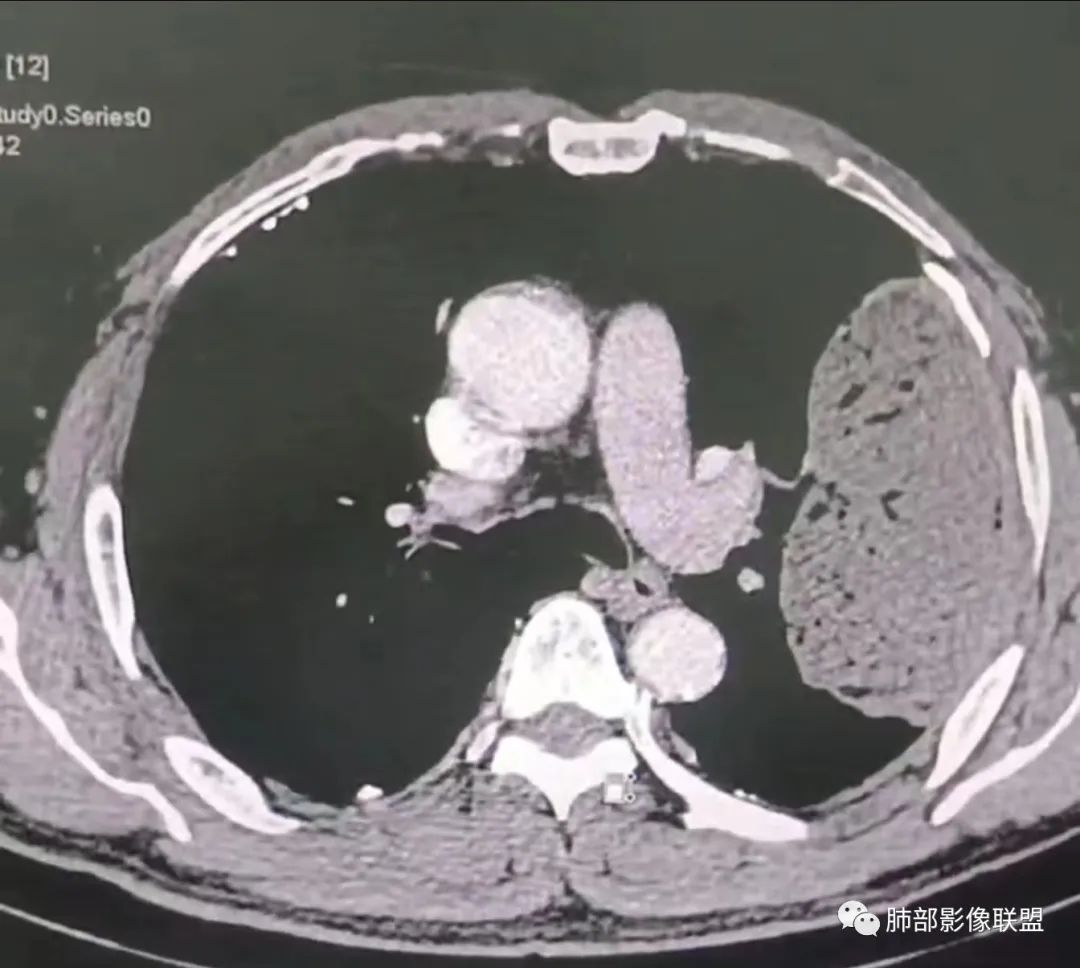

老年男性,糖尿病病史,消瘦、乏力三个月,影像表现左肺上叶胸膜下团块,有一定张力,内部疏松,可见支气管影及坏死区,增强病灶边缘环形强化,内部未见强化,考虑炎性肉芽肿病变,隐球?奴卡?放线菌?鉴别淋巴瘤。

我要修正一下观点了:仔细看了视频,肿块占位效应明显,对周围血管,支气管有推挤,增强后强化不明显,NSE增高,半年体重下降25公斤,虽然有内部支气管扩张,血管漂浮,边界清楚支持淋巴瘤,但强化太低,膨隆,占位推挤太明显(淋巴瘤一般没有这么明显的占位效应),胸膜关系有载桩,恶病质明显(乏力,半年体重下降了25公斤),NSE也明显增高,就不支持淋巴瘤了。还是考虑外朝内的恶性肿瘤,间质来源的肉瘤伴有神经内分泌分化或者大神泌。

不支持淋巴瘤的有四点:1、对周围血管支气管推挤明显。2、胸膜有栽桩,3、强化太弱(淋巴瘤一般还是中度以上甚至高度强化多见),4、NSE升高明显,体重下降太明显。

老年男性,糖尿病病史,消瘦、乏力三个月,肿瘤标志物高。左肺上叶胸膜下肿块,边界清晰,可见支气管影及坏死区,增强病灶边缘强化,内部未见明显强化,邻近胸膜有累及,考虑恶性,建议穿刺活检。

原发性肺肉瘤样癌(PSC)一组临床罕见的肺部肿瘤,属于上皮细胞源性肿瘤,仅占肺部恶性肿瘤的0.3%~4.7%。为含有肉瘤形态细胞或肉瘤样分化的非小细胞肺癌,癌成分多为鳞癌或腺癌,肉瘤成分最常见的是纤维肉瘤。

1)部位:周围型或中央型软组织肿块,以周围型为多见,且肿瘤多位于肺上叶。如本例:该肿瘤位于左肺上叶。

2)大小及形态:由于本病恶性程度高,早期症状不明显,发现时肿块均较大。如本例病变巨大。

4)密度:肿块平扫为软组织密度,由于体积较大,内部常见大片状坏死,可出现不规则厚壁空洞或坏死内多发无壁小空洞,坏死多不均匀:坏死灶内可见如柳絮样的斑片样强化灶,坏死边缘与非坏死区分界不清本例坏死较明显,密度不均匀。

5)肿瘤强化方式:肺部恶性肿瘤强化程度与其血供丰富程度相关,血供丰富多强化明显,反之则较差。由于PSC 周边实性部分富血供及内部黏液变性、坏死,增强后肿块多数呈轻-中度边缘环形强化或不均匀小斑片状强化。国外学者对照病理发现肿瘤细胞或胶原组织增强扫描时强化,无强化的低密度区代表了黏液样变性区和出血坏死区。